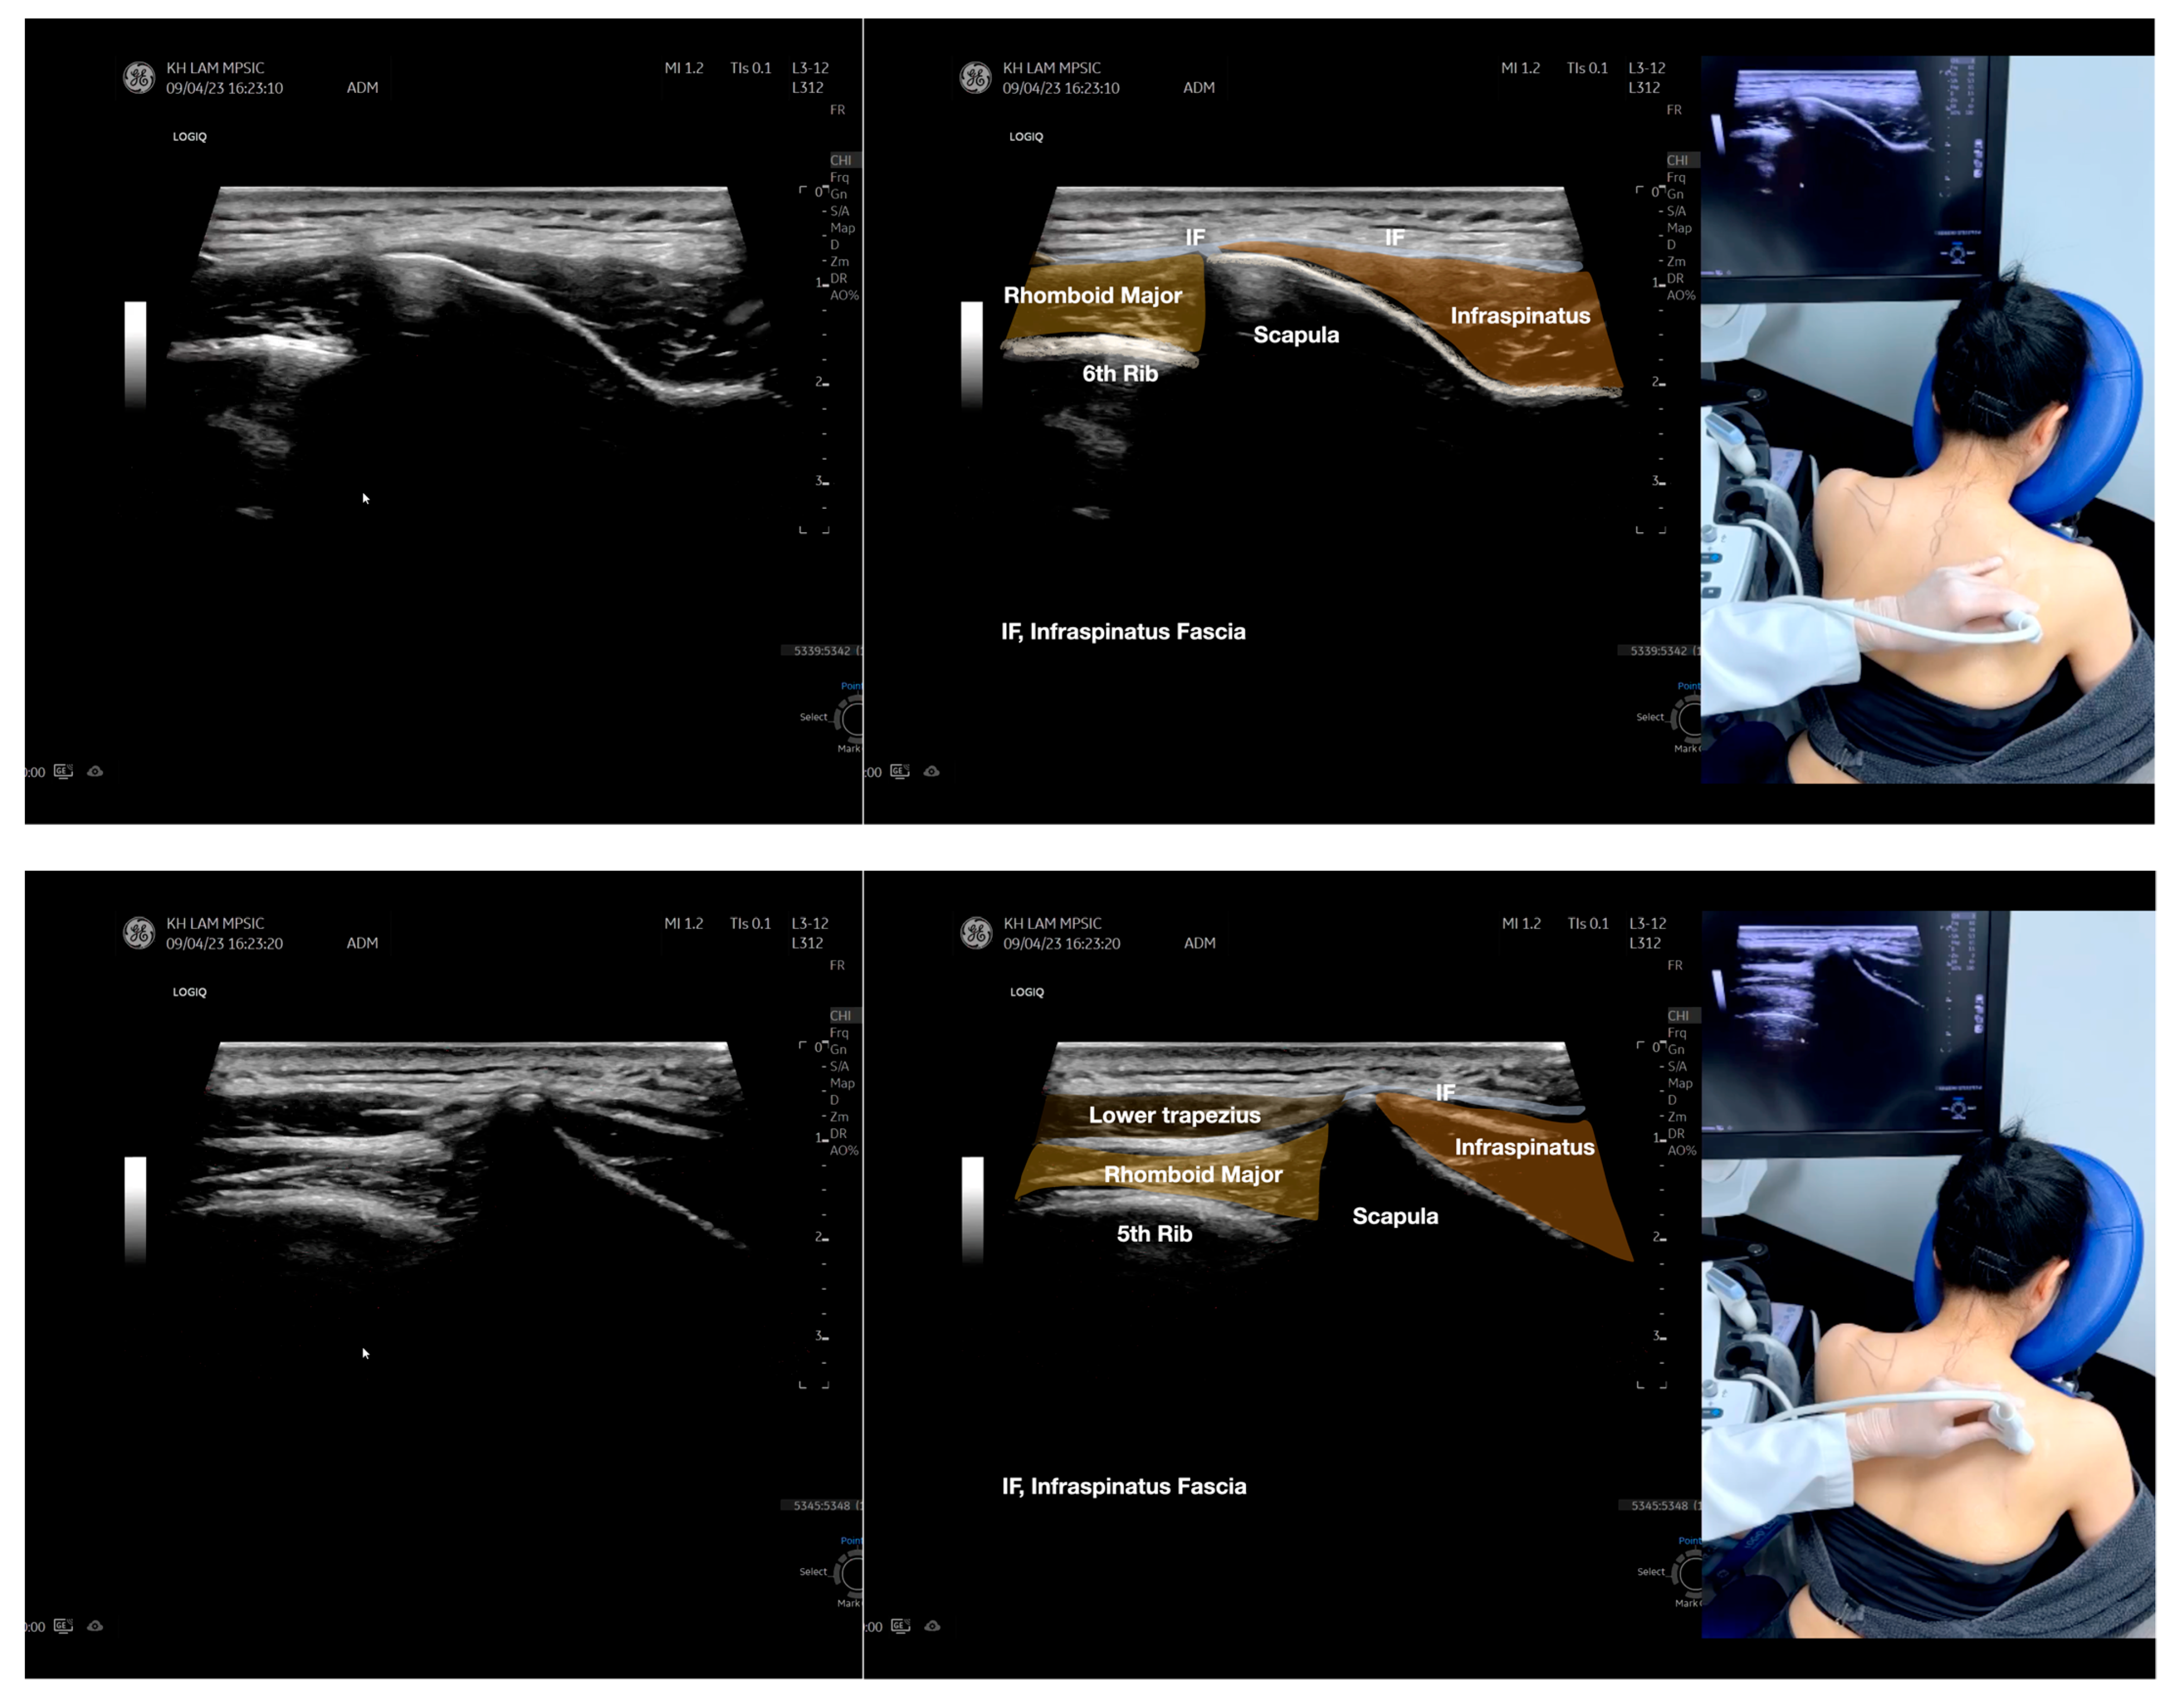

Figure 5.

Sonoanatomy of scanning the infraspinatus fascia in the sagittal plane from the rhomboid minor laterally, then back to the rhomboid major. The step-by-step scanning techniques of the structures illustrated in this figure have been shown in Video S9. Available online: https://www.dropbox.com/s/gu9hhrdq9erin6n/Figure%205.docx?dl=0 (accessed on 1 January 2023).